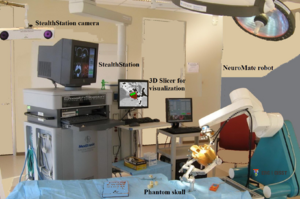

- 3.40 Openigtlink Interface for State Control and Visualisation of a Robot for Image-Guided Therapy Systems

Publication: PLoS One. 2015 Oct 7;10(10):e0139434. PMID: 26444010 | PDF Authors: Tax CM, Chamberland M, van Stralen M, Viergever MA, Whittingstall K, Fortin D, Descoteaux M, Leemans A. Institution: Image Sciences Institute, University Medical Center Utrecht, Utrecht, The Netherlands. Background/Purpose: Fiber tractography plays an important role in exploring the architectural organization of fiber trajectories, both in fundamental neuroscience and in clinical applications. With the advent of diffusion MRI (dMRI) approaches that can also model "crossing fibers", the complexity of the fiber network as reconstructed with tractography has increased tremendously. Many pathways interdigitate and overlap, which hampers an unequivocal 3D visualization of the network and impedes an efficient study of its organization. We propose a novel fiber tractography visualization approach that interactively and selectively adapts the transparency rendering of fiber trajectories as a function of their orientation to enhance the visibility of the spatial context. More specifically, pathways that are oriented (locally or globally) along a user-specified opacity axis can be made more transparent or opaque. This substantially improves the 3D visualization of the fiber network and the exploration of tissue configurations that would otherwise be largely covered by other pathways. We present examples of fiber bundle extraction and neurosurgical planning cases where the added benefit of our new visualization scheme is demonstrated over conventional fiber visualization approaches. Funding: